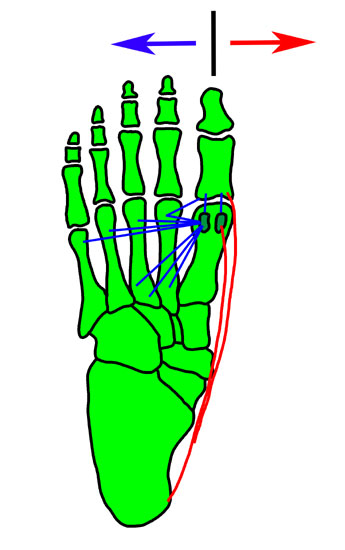

Zusammenhänge der adduzierenden und abduzierenden Muskelkräfte <a class=15, (Janis 1975)" title="Zusammenhänge der adduzierenden und abduzierenden Muskelkräfte 15, (Janis 1975)" width="345" height="550">

Abbildung 6: Zusammenhänge der adduzierenden und abduzierenden Muskelkräfte 15, (Janis 1975)

Ein Hallux varus entsteht am häufigsten durch eine Über­korrektur im Rahmen einer operativen Hallux-valgus-Sanierung (1 – 13 % nach Donley 10; Kelikian, 1961; Mc Elvenny, 1941; Hatori, 1996).

Dabei kommt es zur Störung des muskulären Gleichge­wichtes oder zu einer unphysiologischen Stellung der Knochen des 1. Strahles 16.

Folgende Maßnahmen bei einer Hallux-valgus-Korrektur können ursächlich für die Entstehung eines Hallux varus sein.

• forciertes laterales Release mit

1. Abtrennung des Ansatzes des Muskulus adductor hallucis von der lateralen Basis der Grundphalanx bzw. vom fibularen Sesambein 16

2. laterale Gelenkinzision,

3. Inzision des lateralen Kopfes der kurzen Beugesehen am lateralen Sesambein (McBride, 1954), wobei in der Originaltechnik auch das fibulare Sesambein entfernt wird (Janis, 1995)

4. fast regelhaftes Entstehen eines Hallux varus bei gleichzeitigem Ablösen von M. adductor hallucis und lateralem Kopf des M. flexor hallucis brevis vom fibularen Sesambein;

• übermäßige Korrektur des IM-1-2-Winkels unter 5 – 0° oder bei einem negativen Winkel mit Lateralisation des 1. Mittelfußköpfchens;

• starke mediale Kapselraffung, dabei entsteht oft eine Subluxation des tibialen Sesambeines nach medial;

• übermäßige Resektion der Pseudoexostosen, damit Verlust des Abstützens der Grundphalanx am Mittelfußköpfchen;

• aggressive postoperative Zügelung der Großzehe nach medial mittels Bandage, Schiene oder Tape,